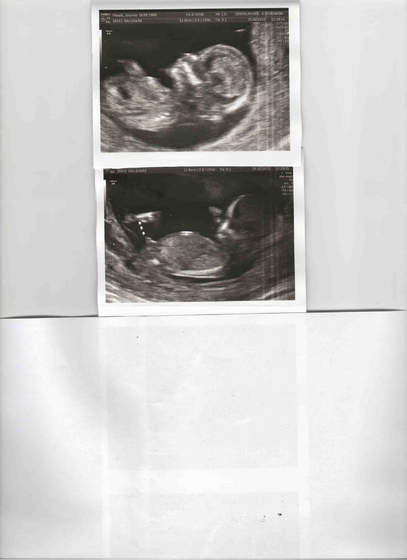

oglądam te wszystkie linki o nube i nasz wygląda tak SAM_1890.jpg fota z 12t2d co sądzicie o naszym nub? :-)